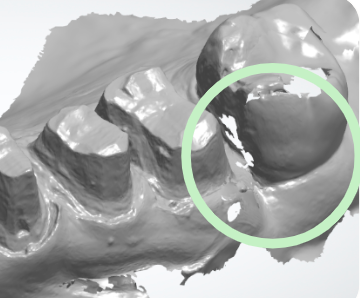

Contactos interproximales

• Escaneo completo de contactos - Verifique que no haya datos faltantes y que tanto los contactos mesiales como distales de la futura corona estén completamente escaneados.

• Puntos de contacto suaves - Asegúrese de que los puntos de contacto mesial y distal sean lisos, sin apariencias dentadas o irregulares.

• Si es necesario, suavice todos los bordes dentados, recorte el escaneo con la herramienta de recorte y vuelva a escanear antes de enviar el caso.

• Técnicas para áreas difíciles - Use la técnica de giro para capturar áreas interproximales difíciles y subgingivales profundas.